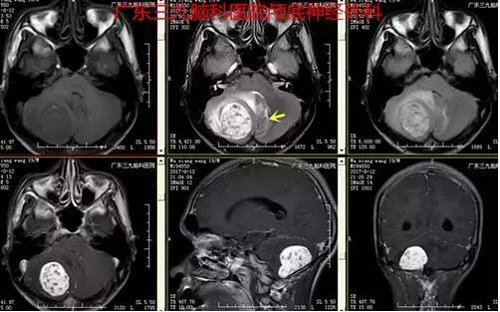

图2:术前MR提示右侧小脑团块状长T1长T2为主异常信号影、间杂多发斑点状短T1短T2信号影以及流空血管影,范围约4.4cm×3.0cm×3.7cm,增强后呈欠均匀明显强化

上述案例为实质性血管母细胞瘤,术前MR提示右侧小脑半球类圆形占位,增强明显强化,中见血管流空影,考虑血管母细胞瘤,予手术前行造影提示病变区域大片异常染色,主要由右侧脑膜后动脉、右侧椎动脉颈部分支、右侧小脑后下动脉等参与供血,予栓塞右侧椎动脉颈部分支,栓塞顺利,栓塞后造影提示肿瘤区域染色明显减少。随即送手术室行肿瘤切除,术中见右侧小脑类似血管团病变,类圆形,术中出血少,肿瘤切除时间约10分钟,手术顺利,术后患者恢复快,未有明确并发症,现恢复良好出院。